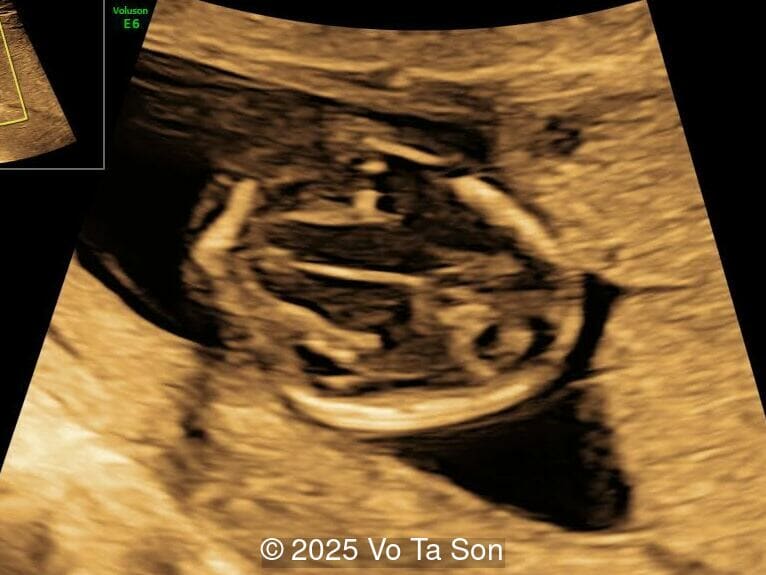

Our imaging revealed the following significant fetal abnormalities:

• Ventricular septal defect (VSD)

• Tricuspid valve regurgitation

• Right aortic arch